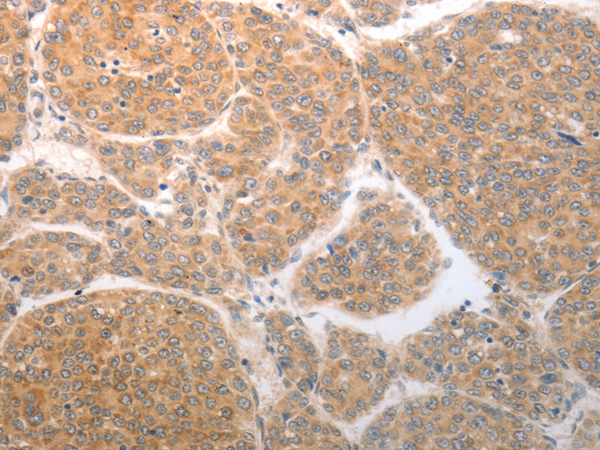

分类: 科研抗体货号: P11283别名:应用: WB,IHC反应种属: Human, Mouse